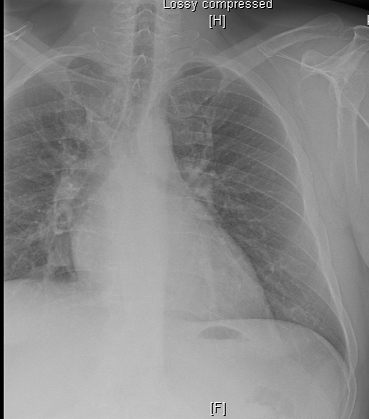

Chest X-Ray